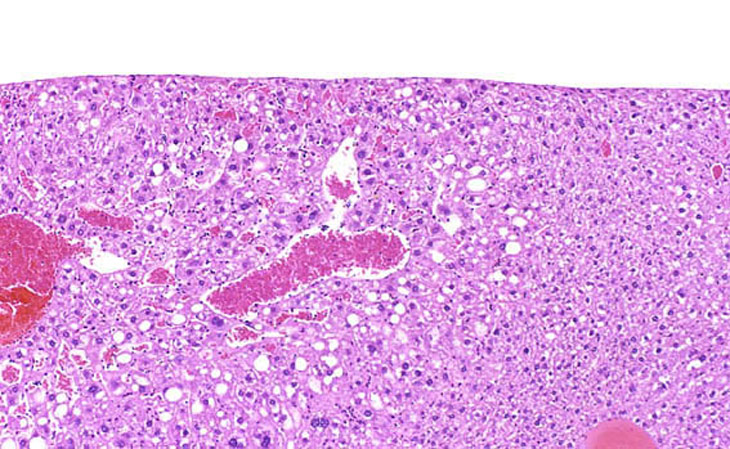

Angiectasis (peliosis hepatis, telangiectasis) is an incidental finding occasionally noted in aging mice. In extensive lesions, atrophy of adjacent hepatocytes may be seen. The lesions consists of dilated sinusoidal spaces lined by normal endothelial cells and filled with blood cells in immersion-fixed specimens. This lesion is occasionally associated with hepatocellular neoplasms. Angiectasis typically consists of smaller blood channels than is seen in hemangiomas. Also, angiectatic vascular channels are often not associated with endothelial cell proliferation as is seen in hemangiomas.

These examples represent low magnification views of angiectasis.

These examples represent medium magnification views of angiectasis.